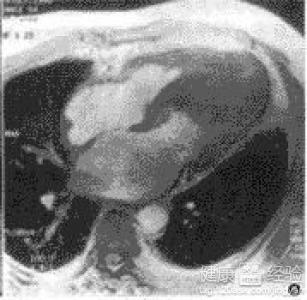

摘要:關(guān)于擴(kuò)張性心肌病的最新治療,小巷深處的隱藏寶藏正逐漸為人們所發(fā)現(xiàn)。通過(guò)先進(jìn)的醫(yī)療技術(shù)和方法,擴(kuò)張性心肌病的治療取得了新的進(jìn)展。這些治療方法旨在改善心臟功能,提高患者生活質(zhì)量。小巷深處的醫(yī)療機(jī)構(gòu)或?qū)<铱赡茈[藏著寶貴的治療經(jīng)驗(yàn)和方法,為尋求最佳治療方案的病患帶來(lái)希望。更多詳細(xì)信息需要進(jìn)一步探索和研究。

擴(kuò)張性心肌病是一種嚴(yán)重的心臟疾病,但“心之港灣”為你帶來(lái)希望,這里的專家團(tuán)隊(duì)一直在深入研究擴(kuò)張性心肌病的最新治療方法,并深知每位患者都渴望得到最佳的治療和關(guān)懷,他們努力不懈,為患者帶來(lái)生機(jī)和新生。